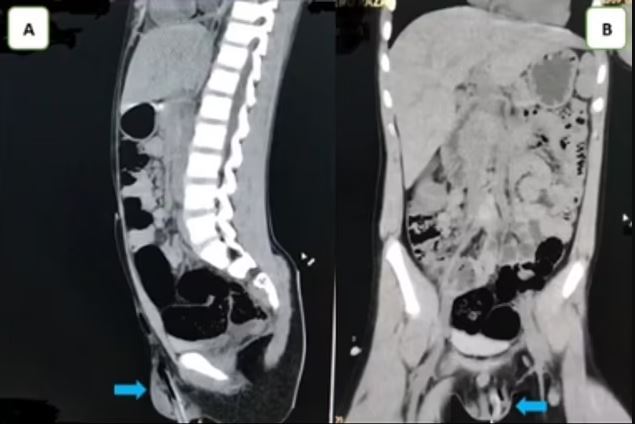

Bitter pictures show that the stick has penetrated to the left below his elbow, and has reached the navel bone.

Doctors scanned the area to confirm that her testicles were not damaged before the stick was removed.